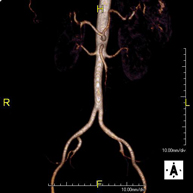

Prova diagnòstica no invasiva que consisteix en l'obtenció d'imatges d'alta definició anatòmica de tot el cos mitjançant l'ús d'un camp electromagnètic i ones de ràdio (amb un emissor i un receptor). No utilitza radiació ionitzant. És una prova molt important en la recerca de metàstasi en pacients amb neoplàsia coneguda. No requereix preparació prèvia. No és necessari l'ús de contrast paramagnètic (Gadolini). - Angio RM d'Aorta-ilíaca

Prova diagnòstica no invasiva que consisteix en l'estudi de l'artèria aorta abdominal i de les artèries ilíaques, amb l'obtenció d'imatges d'alta definició anatòmica mitjançant l'ús d'un camp electromagnètic i ones de ràdio (amb un emissor i un receptor). És indispensable l'ús de contrast paramagnètic (Gadolini). No utilitza radiació ionitzant. La qualitat de les imatges permet realitzar reconstruccions en 2D i 3D. Aquesta prova està especialment indicada com a estudi prequirúrgic (mapa vascular) abans d'intervencions percutànies o quirúrgiques d'aorta abdominal i artèries ilíaques, per a l'estudi complementari en pacients amb isquèmia de membres inferiors, etc. - Angio RM Arterial d'extremitats inferiors

Prova diagnòstica no invasiva que consisteix en l'estudi de l'artèria aorta abdominal per obtenir imatges d'alta definició anatòmica mitjançant l'ús d'un camp electromagnètic i ones de ràdio (amb un emissor i un receptor). És indispensable l'ús de contrast intravenós paramagnètic (Gadolini). No obstant, no utilitza radiació ionitzant. La qualitat de les imatges permet realitzar reconstruccions en 2D i 3D. Està indicat en aquells pacients amb malaltia vascular (Aterosclerosi), per a l'estudi d'aneurismes, en estudis prequirúrgics de lesions adjacents a l'aorta abdominal com "mapa" vascular, etc. - Angio-RM Aorta ilíaca

Prova diagnòstica no invasiva que consisteix en l'estudi de l'artèria aorta abdominal per obtenir imatges d'alta definició anatòmica mitjançant l'ús d'un camp electromagnètic i ones de ràdio (amb un emissor i un receptor). És indispensable l'ús de contrast intravenós paramagnètic (Gadolini). No obstant, no utilitza radiació ionitzant. La qualitat de les imatges permet realitzar reconstruccions en 2D i 3D. Aquesta prova està especialment indicada com estudi prequirúrgic (mapa vascular) abans d'intervencions percutànies o quirúrgiques d'aorta abdominal, per a l'estudi complementari en pacients amb isquèmia de membres inferiors, etc. - Angio-RM d'Artèries renals